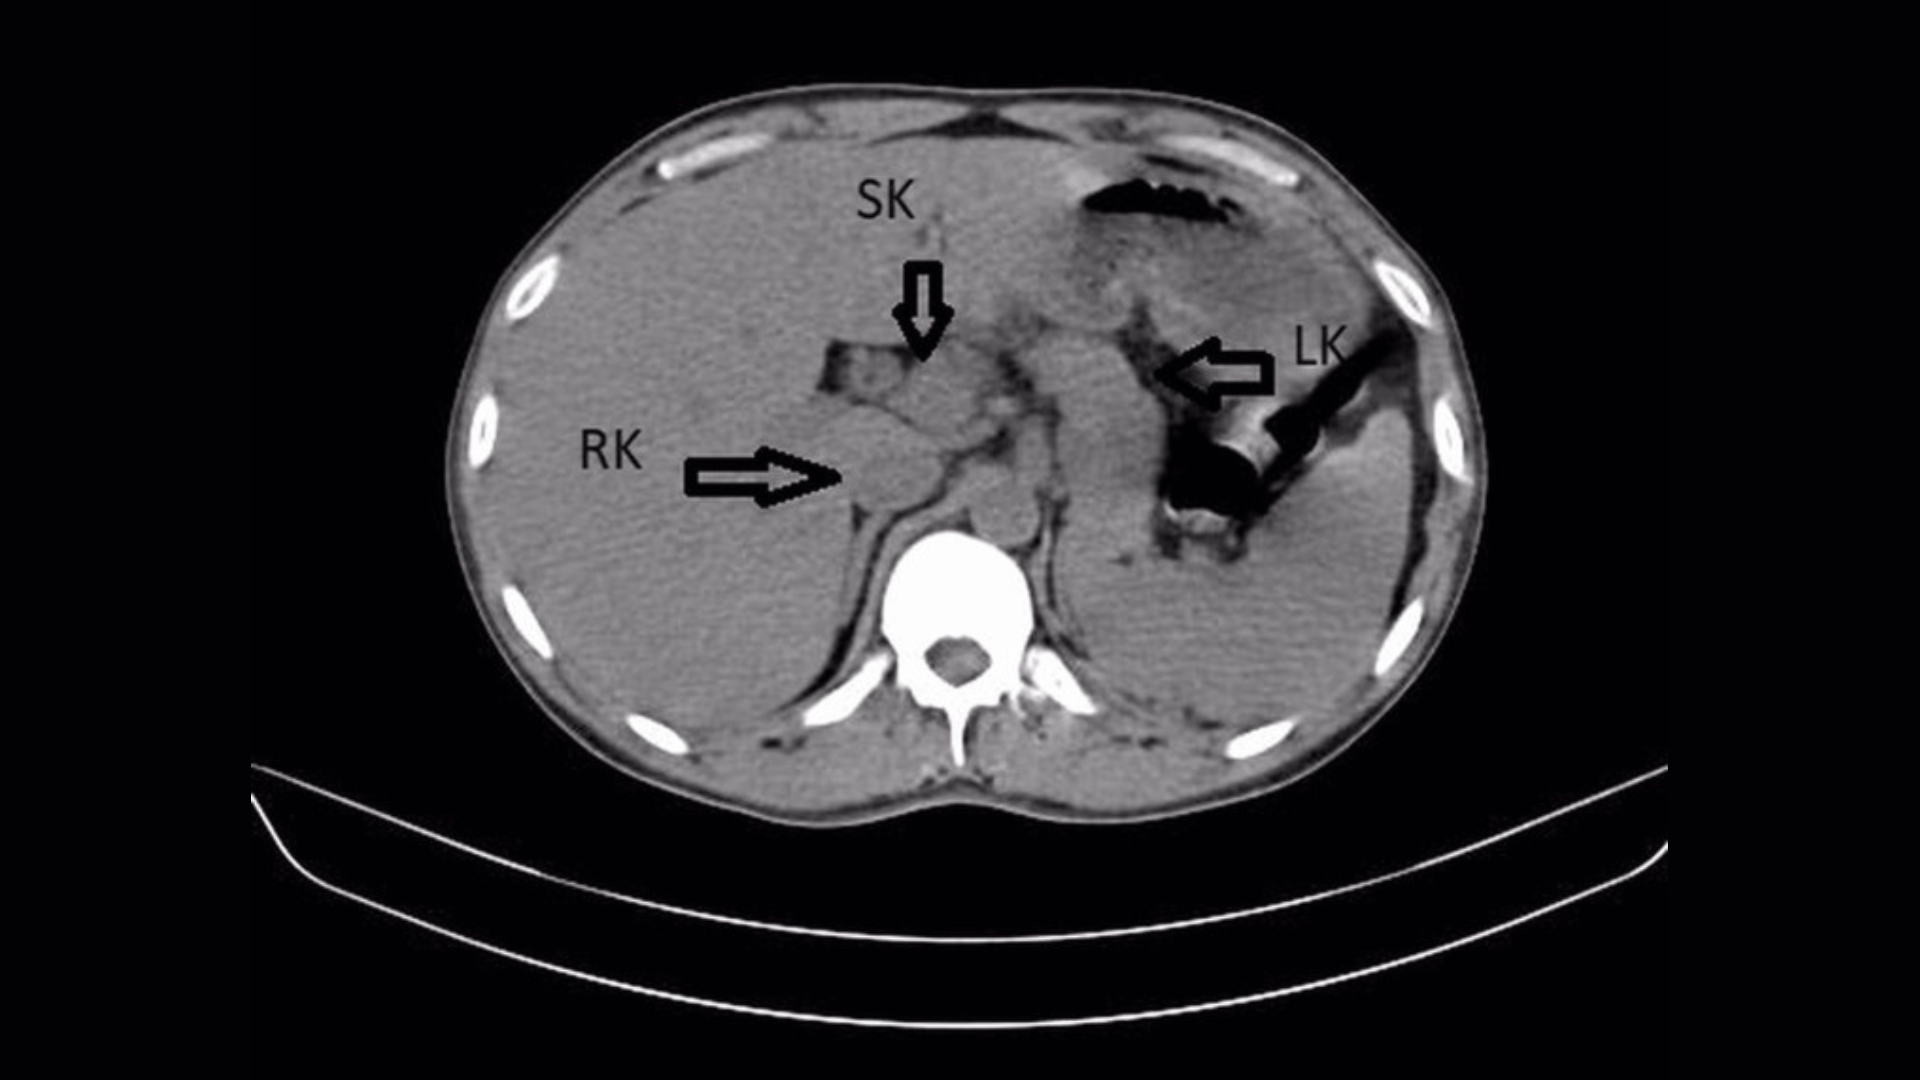

Le diagnostic : Ils se sont demandé si les symptômes indiquaient La maladie d’Addisonqui affecte les glandes surrénales situées au-dessus des reins. Ces glandes produisent normalement des hormones qui aident à contrôler la réponse au stress, la tension artérielle et l’équilibre eau-sel dans le corps, mais chez les patients atteints de la maladie d’Addison, elles ne produisent pas suffisamment d’hormones. C’est le plus souvent causé par une réponse auto-immunedans lequel le système immunitaire attaque les glandes surrénales et compromet leur fonction.

Les tests ont montré que le patient était porteur d’anticorps contre les glandes surrénales, ce qui suggère qu’une telle réponse auto-immune se déroulait. De plus, elle présentait des taux élevés d’hormone adrénocorticotrope (ACTH), un signal que le cerveau envoie pour tenter d’augmenter l’activité des glandes surrénales ; et la rénine, que les reins produisent lorsque l’équilibre eau-sel du corps est perturbé.